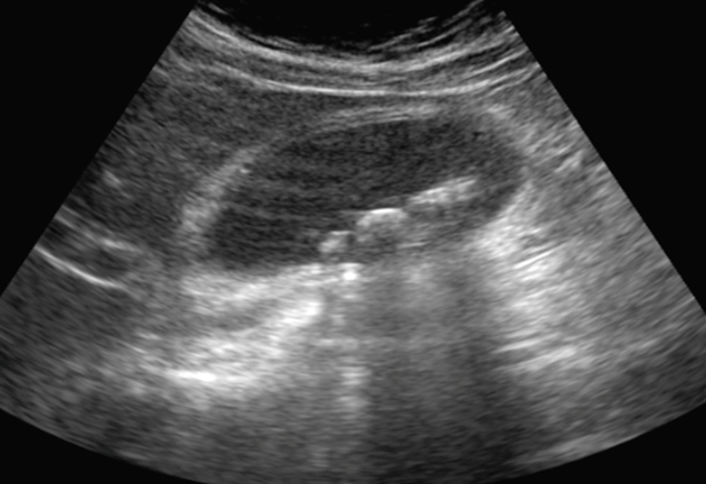

US Gall bladder in the picture and findings as follows:

US abdomen

GB wall thickening (>4-5 mm) or oedema (double wall sign)

Acoustic shadowing

No CBD dilation (CBD not often seen – or reliable)

“Sonographic Murphy’s sign“ positive

What is the most likely diagnosis?

Acute Cholecystitis